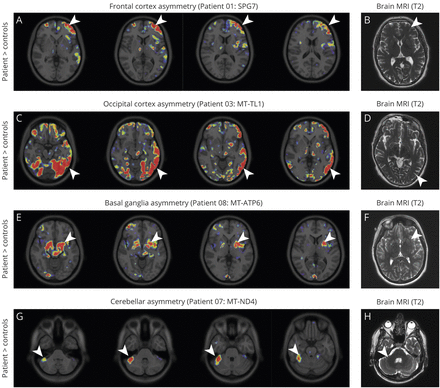

不对称的11C] P188金宝慱官网下载K11195绑定

许多(11C] P188金宝慱官网下载K11195宠物画面显示不对称信号改变大脑的特定区域(图5),没有明显的对应相应的MRI异常。最明显的例子不对称的放射性示踪剂绑定在大脑皮层(额叶皮层在病人1SPG7突变;枕叶皮质区和一个病人3MT-TL1突变;图5 A和C),基底神经节(病人8,MT-ATP6突变;图5 e7)或小脑(患者MT-ND4突变;图5克)。不对称信号变化不明确相关临床表现,在图中以增加信号的对侧小脑半球LHON患者(患者7;图5克)否则无症状(表)。